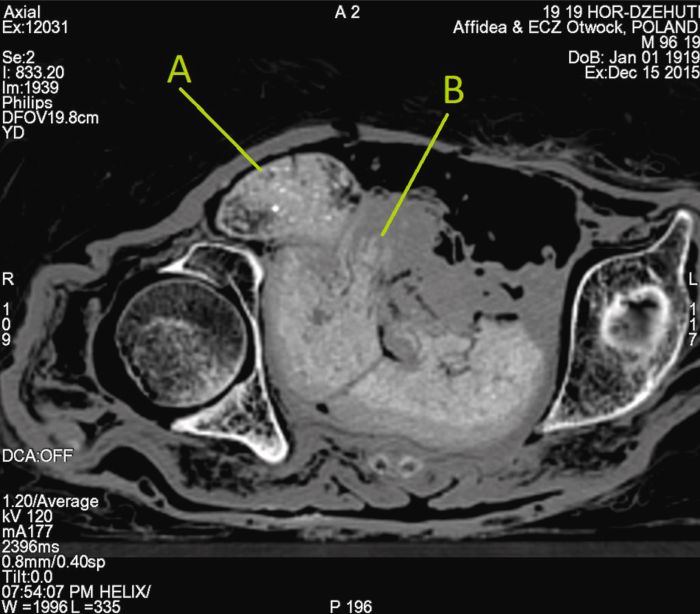

Molto famoso in tempi recenti è diventato anche il feto di sette mesi scoperto nel corpo di una mummia conservata al Museo di Varsavia (“Mysterious Lady”), ritenuta in passato il sacerdote di Horus Hor-Djehuty dalle iscrizioni sul sarcofago che la conteneva, ma non sappiamo ad oggi se la morte della mamma sia stata dovuta alla gravidanza.